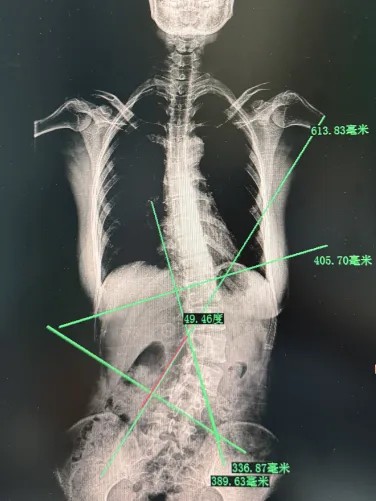

DR影像顯示:

1、脊柱下胸椎及腰椎“S”形側(cè)彎、旋轉(zhuǎn)。

2、頸椎曲度改變。

經(jīng)過站立位全脊柱X線檢查,文女士(化名)的脊柱側(cè)彎進(jìn)一步明確,而且不僅有側(cè)彎(側(cè)彎49.46度),還有腰椎間盤突出,是由發(fā)育期不良坐姿導(dǎo)致的。